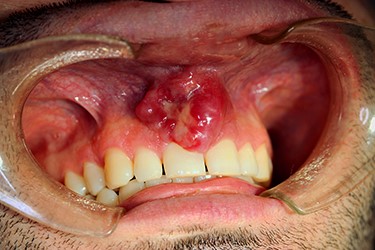

On examination, a lobulated, firm mass was seen extruding from the anterior maxillary vestibule (Fig. 1). All maxillary teeth were painless to percussion, and normal tooth mobility was present. No cervical lymphadenopathy was detected, nor any changes with cranial nerve examination. A maxillofacial computerized tomographic (CT) scan revealed an osteolytic lesion on the maxillary alveolar process (Fig. 2).

Surgical access was obtained intraorally, and an en bloc resection of the premaxilla was performed (Fig. 3). Histopathological examination confirmed the diagnosis, revealing a completely resected MCS with clear margins (Fig. 4).